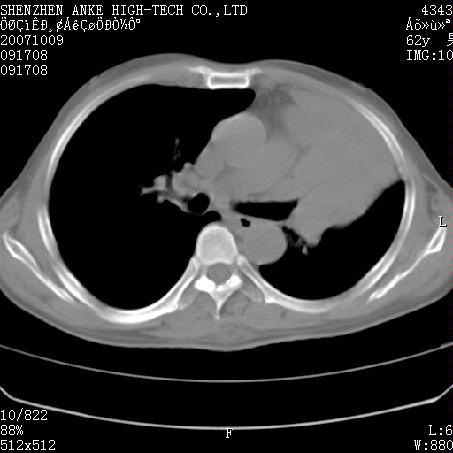

患者:男,62岁,咳嗽、胸痛、咯血约2月

左侧中央型肺癌伴上叶肺不张\\阻塞性肺炎.

左侧中央型肺癌伴上叶肺不张、阻塞性肺炎、纵隔淋巴结转移。支持!

左侧中央型肺癌伴上叶肺不张及阻塞性肺炎,纵隔内淋巴结转移